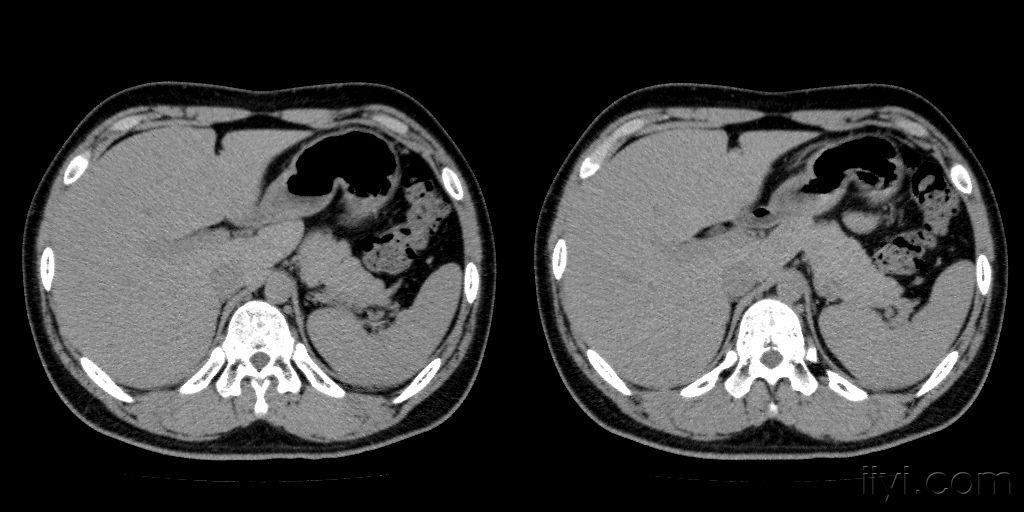

正常胰腺,周围脂肪间隙清晰

图片尺寸2667x2000